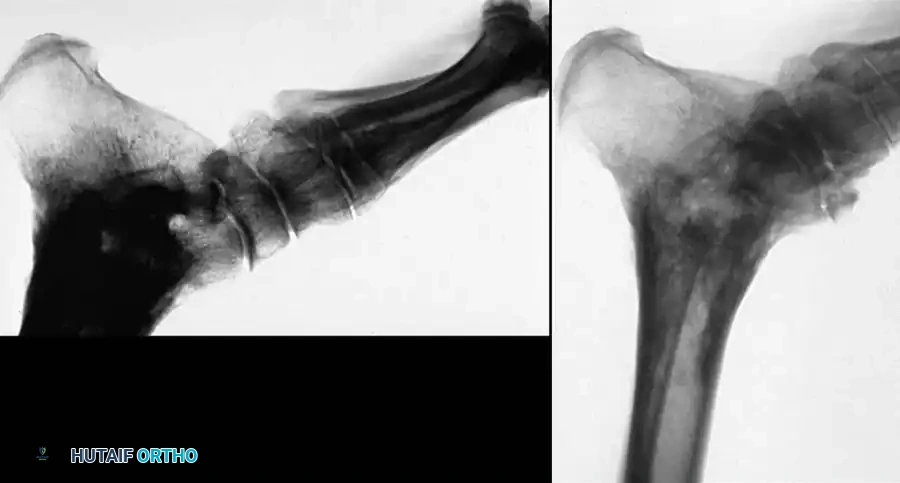

• Type I: Nondisplaced vertical fracture of the talar neck. The subtalar, tibiotalar, and talonavicular joints remain congruous. AVN risk is historically 0-10%.

• Type II: Displaced fracture of the talar neck with subluxation or dislocation of the subtalar joint. The ankle joint remains aligned. AVN risk is 20-50%.

• Type III: Displaced fracture of the talar neck with dislocation of both the subtalar and tibiotalar (ankle) joints. The talar body is often extruded posteromedially. AVN risk is 50-90%.

• Type IV: (Added later by Canale and Kelly). Displaced fracture of the talar neck with dislocation of the subtalar, tibiotalar, and talonavicular joints. The head of the talus is subluxed or dislocated. AVN risk approaches 100%.

Displaced talar neck diagram